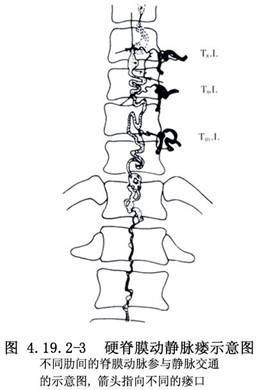

硬脊膜血管畸形亦稱硬脊膜動靜脈畸形(spinal dural AVMs),目前,多稱爲硬脊膜動靜脈瘻(spinal dural arteriovenous fistulae)。由於選擇性脊髓血管造影的開展和顯微手術的應用,對本病的發現率已明顯增加。畸形血管中含有供血動脈和引流靜脈,以及動靜脈之間的異常分流,亦可有畸形血管團。脊髓功能障礙症狀的產生,主要是脊髓的迴流靜脈內有動脈血的注入,使迴流靜脈內的壓力不斷升高所致。Symon(1984)報告的78例椎管內AVM中有55例位於硬脊膜或與硬脊膜表面有連屬。Rosenblum(1987)報告的81例中,硬脊膜AVM佔33%。其與硬脊膜內或脊髓AVM的不同點是:①本病好發於高齡病人,平均年齡爲59歲;②是後天性疾病;③多以疼痛和進行性癱瘓爲首發症狀,極少發生出血;④供血動脈均來自肋間動脈或腰動脈的硬脊膜分支;⑤病竈多位於椎間孔區,畸形血管團或動靜脈瘻埋置在覆蓋神經根及其附近的硬脊膜中,可有增粗且動脈化的引流靜脈穿過硬脊膜,紆曲走行於脊髓表面,與脊髓冠狀靜脈及靜脈叢相連屬(圖4.19.2-1);⑥手術比脊髓AVM簡單,只要將動靜脈間的分流阻斷或將病竈局部切除即可獲得良好效果,不必廣泛切除引流靜脈。供血動脈的人工栓塞術效果也較好(圖4.19.2-2,4.19.2-3)。